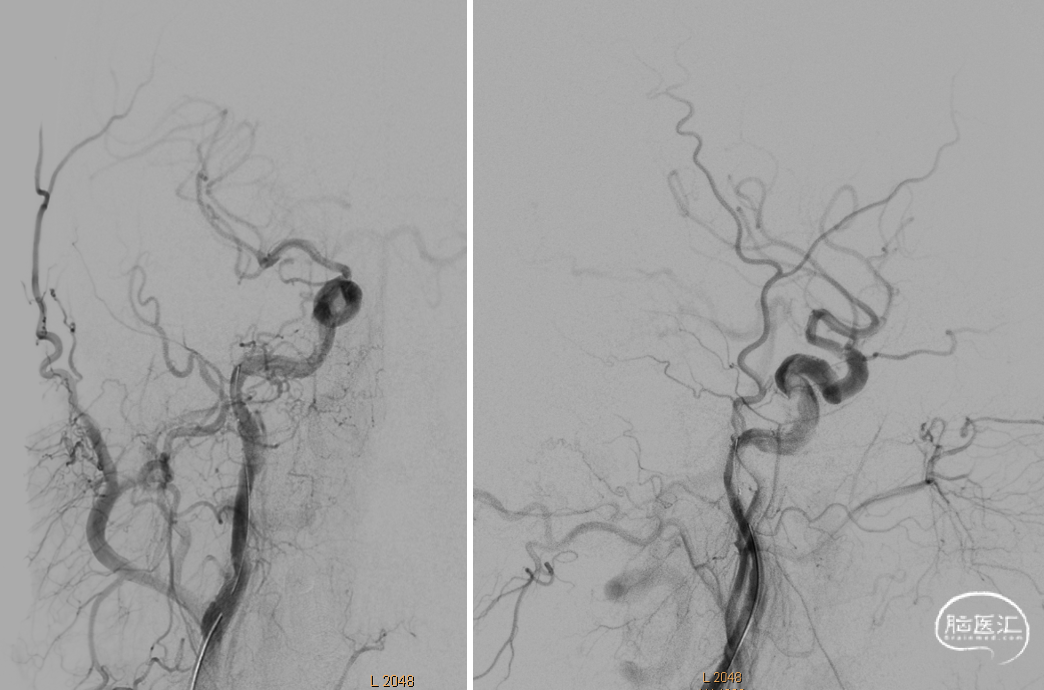

DSA提示右侧颈内动脉闭塞